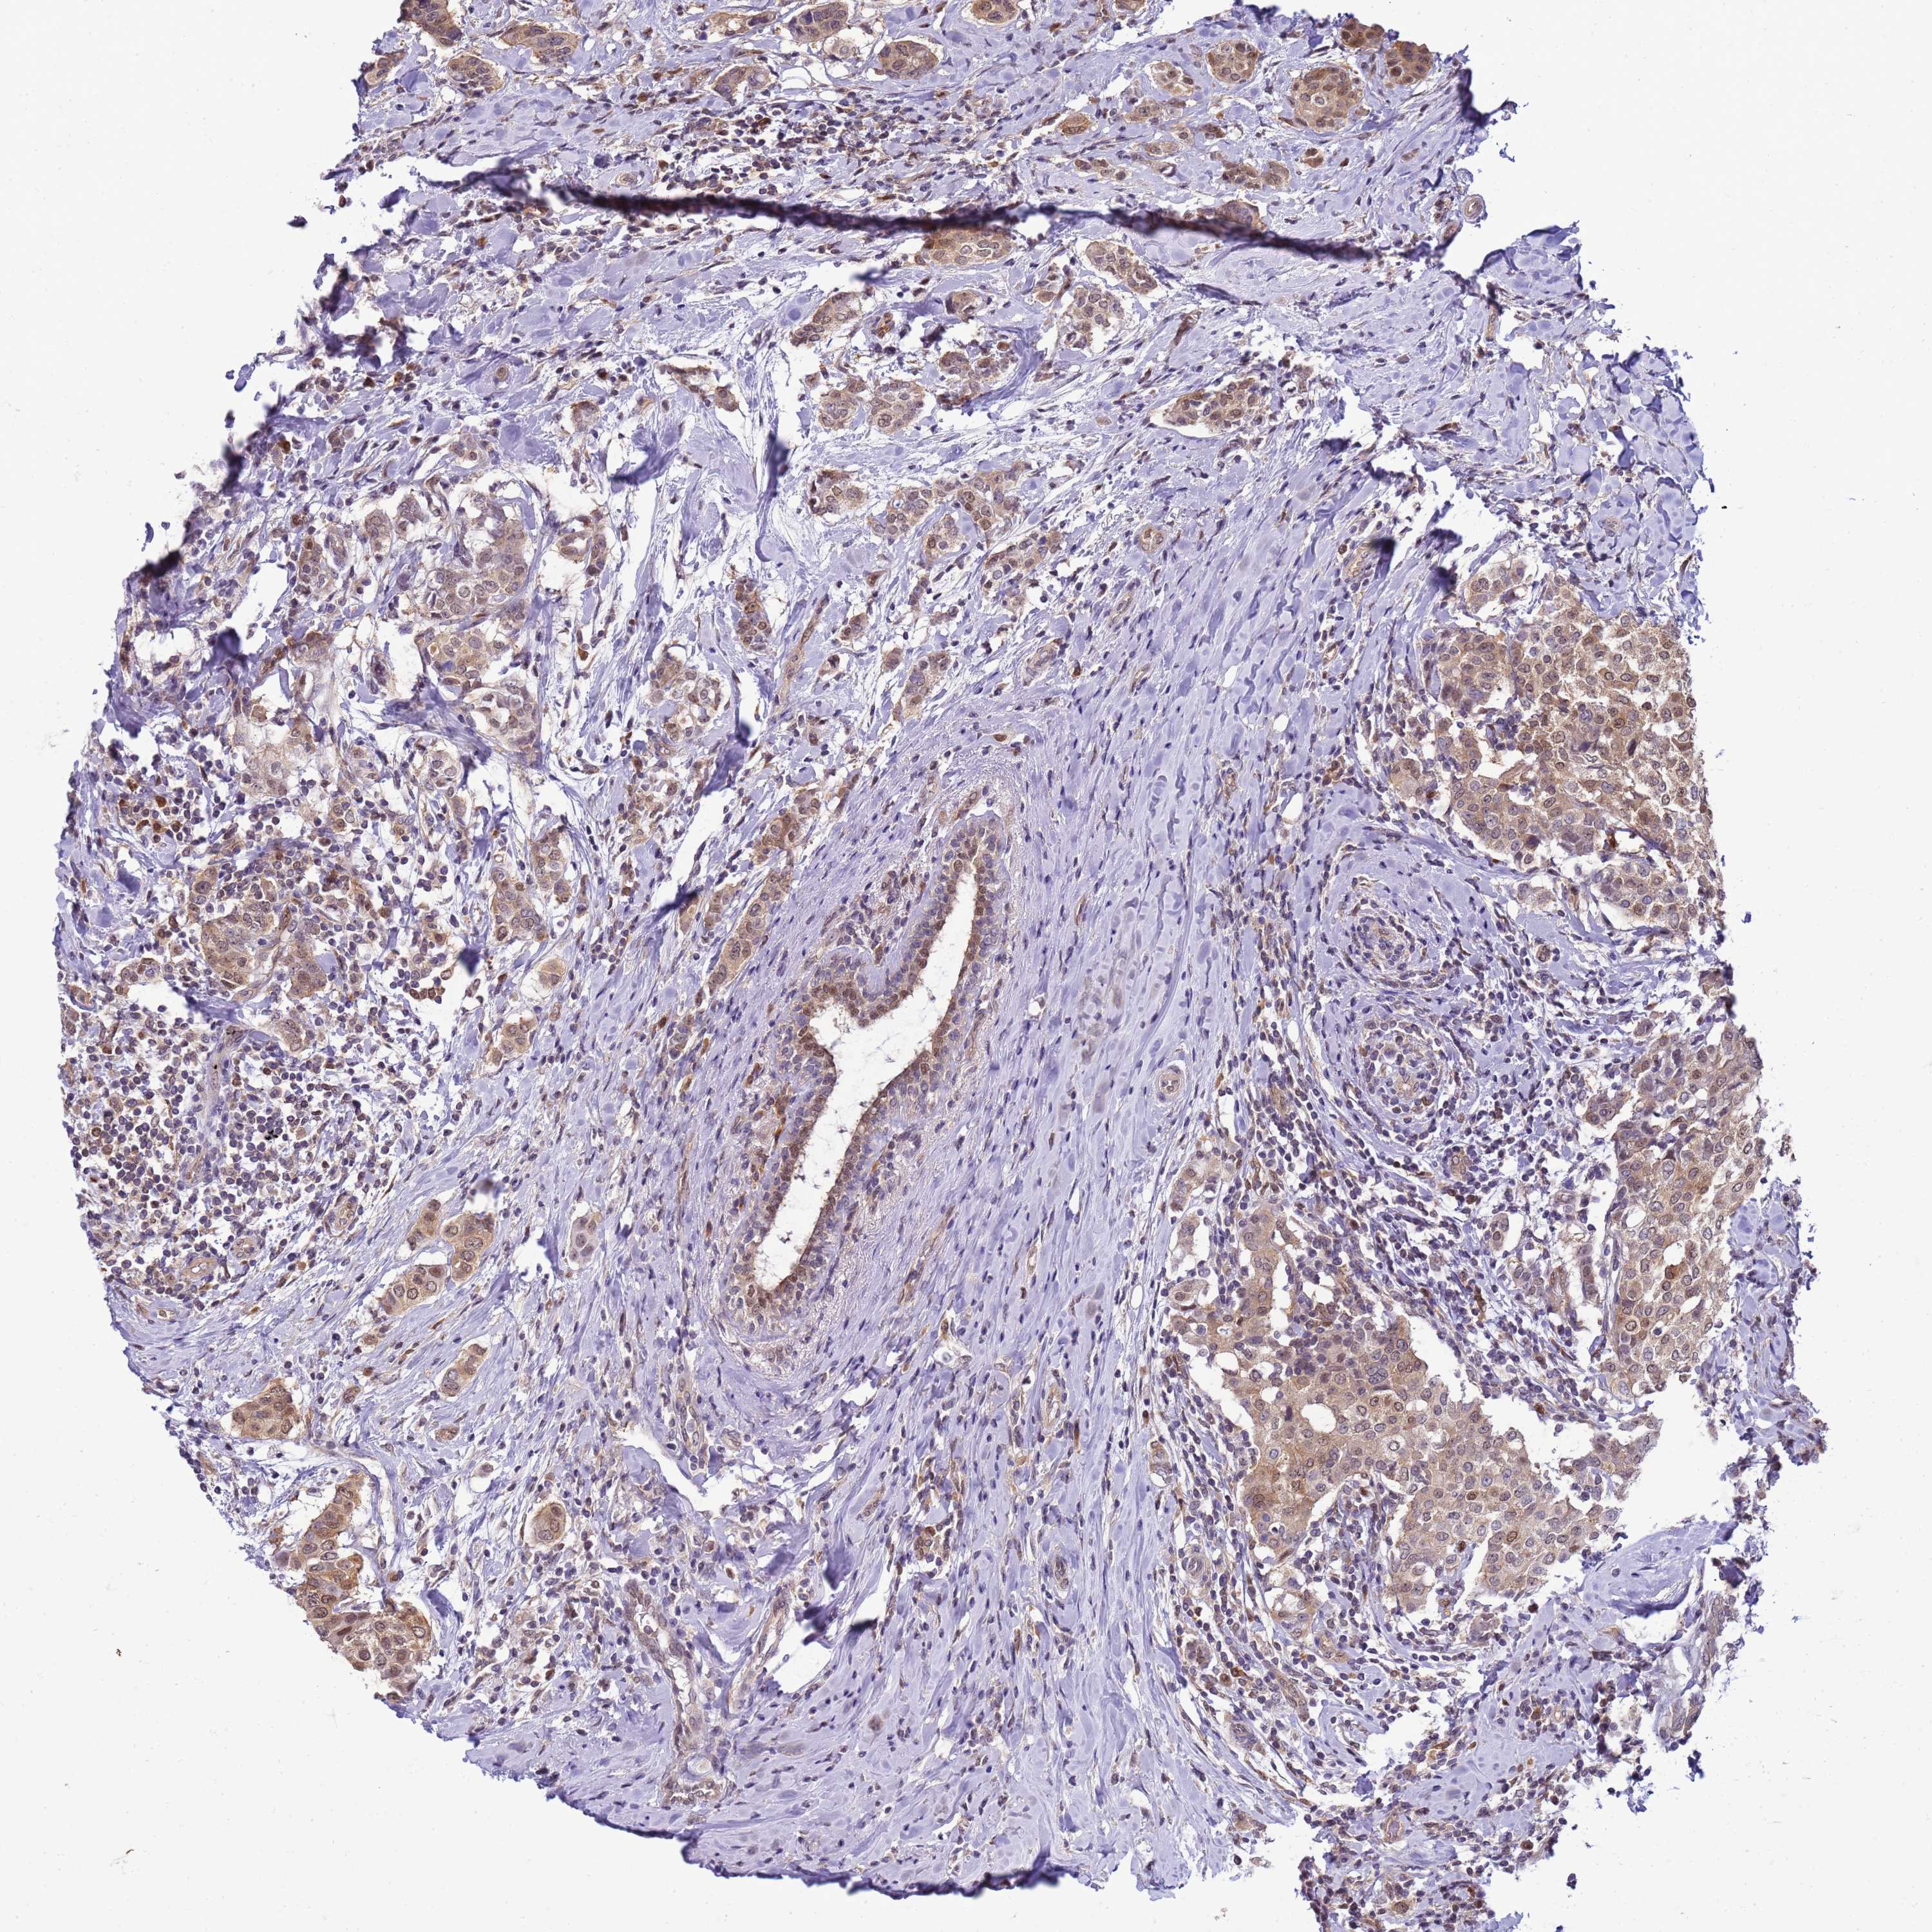

CANCER BREAST CANCER Show tissue menu

BRCA TCGA BRCA VALIDATION PROTEIN EXPRESSION

ANTIBODIES

AND

VALIDATION